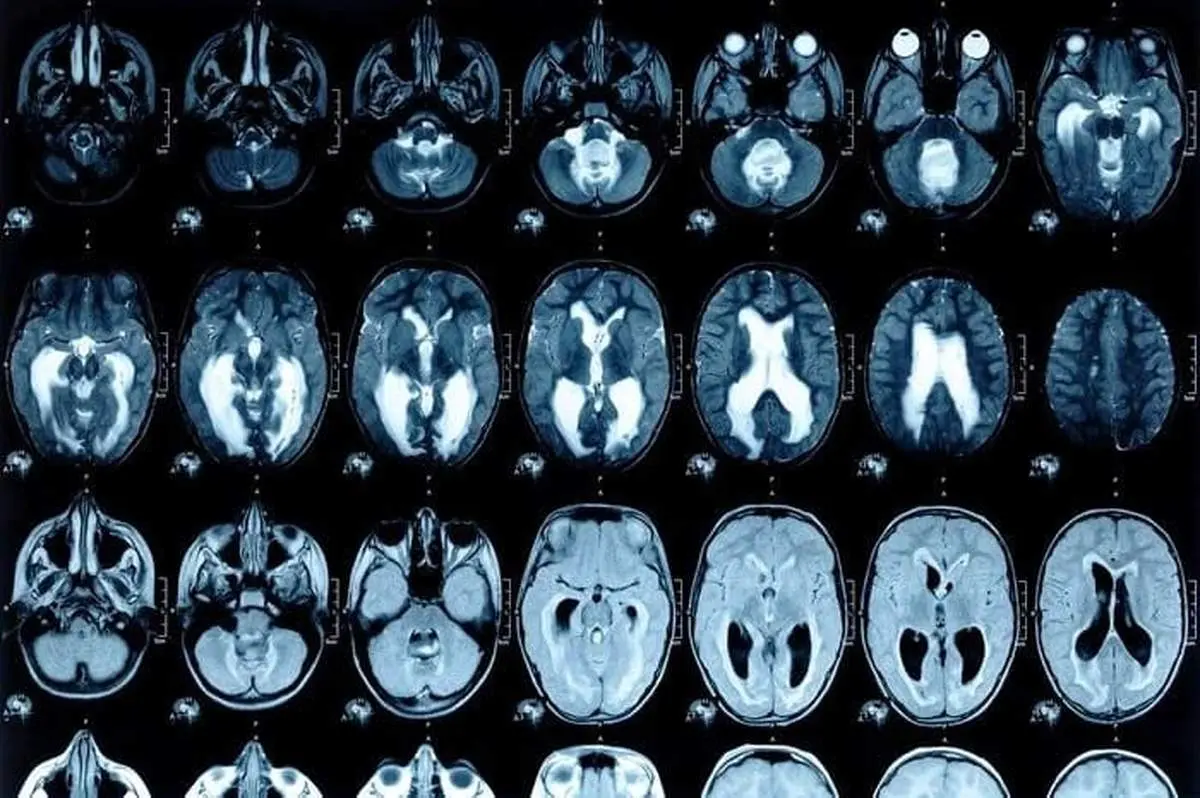

پزشکان پس از اسکن سر زن باردار این موضوع را به تایید رساند که در جمجمه اش میخی فرو رفته؛ سپس این خانم را در بیمارستان بستری کردند. زمانی که علت را از او پرسیدند، گفت که از دیگران شنیده بود که اگر این کار را انجام دهد، حتماً فرزند پسر به دنیا می آورد.

این زن به طرز هولناکی، فرو کردن میخ آهنی داخل جمجمه را خودش با چکش انجام داده و دچار زخم و خونریزی شدید شد بنابراین نتوانست کارش را به پایان رسانده و با وخیم شدن وضعیتش، به همین شکل به بیمارستان مراجعه کرد. میخ فرورفته داخل جمجمه این زن، با تلاش یک تیم پزشکی خارج شد و او در حال حاضر در وضعیت بهتری قرار دارد.